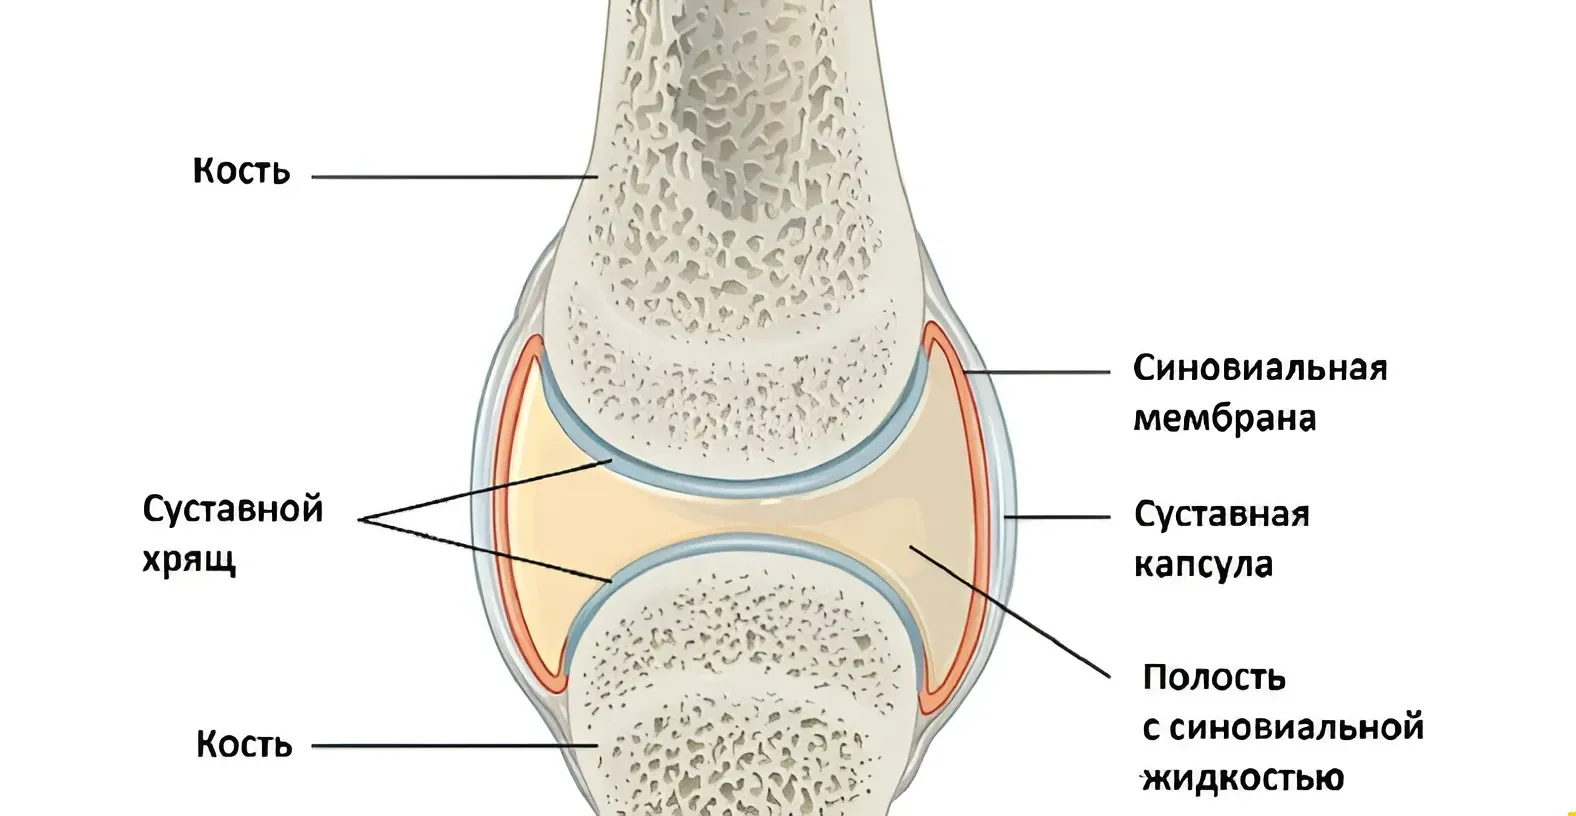

Диаграммы и схемы движения в суставах человека